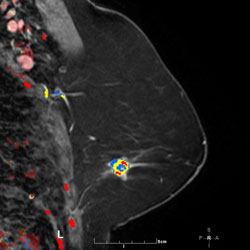

MR Angiomap

A right breast invasive lobular cancer (Estrogen Receptor/Progesterone Receptor +, Her-2 neu -).

Ultrasound demonstrates a dominant spiculated and irregular hypoechoic mass

Ultrasound demonstrates a dominant spiculated and irregular hypoechoic mass with dense posterior shadowing (known cancer). There were adjacent, similar-appearing hypoechoic irregular, spiculated masses present also.

MIP (Maximum Intensity Projection) image of MR

MIP (Maximum Intensity Projection) image of MR shows the known cancer: irregularly marginated mass in the upper outer to central breast. Satellite subcentimeter nodules are present anteromedially and posteriorly.